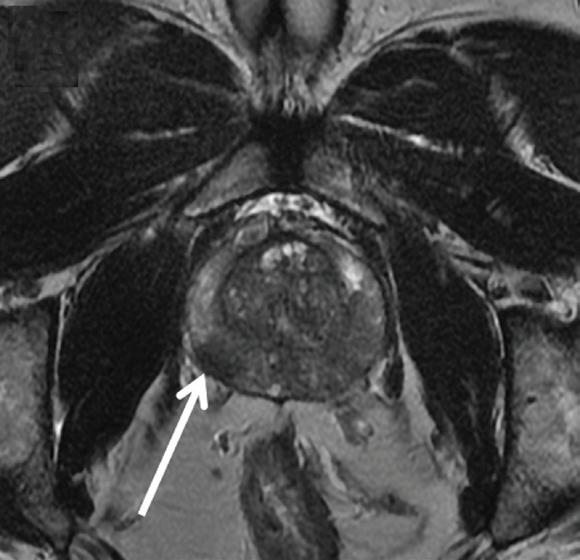

above: A 63-year-old man with right-side prostate cancer (shown by arrows) detected on 3T MRI of the prostate. Image D shows curves for average and worse pixels in the tumor. All images provided by Mount Sinai’s Department of Radiology and Translational and Molecular Imaging Institute.